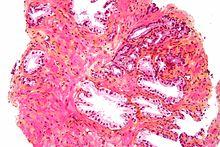

Micrograph of benign prostatic glands with corpora amylacea. H&E stain.

The prostate consists of glandular and connective tissue.[1] Tall column-shaped cells form the lining (the epithelium) of the glands.[1] These form one layer or may be pseudostratified.[3] The epithelium is highly variable and areas of low cuboidal or flat cells can also be present, with transitional epithelium in the outer regions of the longer ducts.[9] The glands are formed as many follicles, which in drain into canals and subsequently 12–20 main ducts, These in turn drain into the urethra as it passes through the prostate.[3] There are also a small amount of flat cells, which sit next to the basement membranes of glands, and act as stem cells.[1]

The connective tissue of the prostate is made up of fibrous tissue and smooth muscle.[1] The fibrous tissue separates the gland into lobules.[1] It also sits between the glands and is composed of randomly orientated smooth-muscle bundles that are continuous with the bladder.[10]

Over time, thickened secretions called corpora amylacea accumulate in the gland.[1]